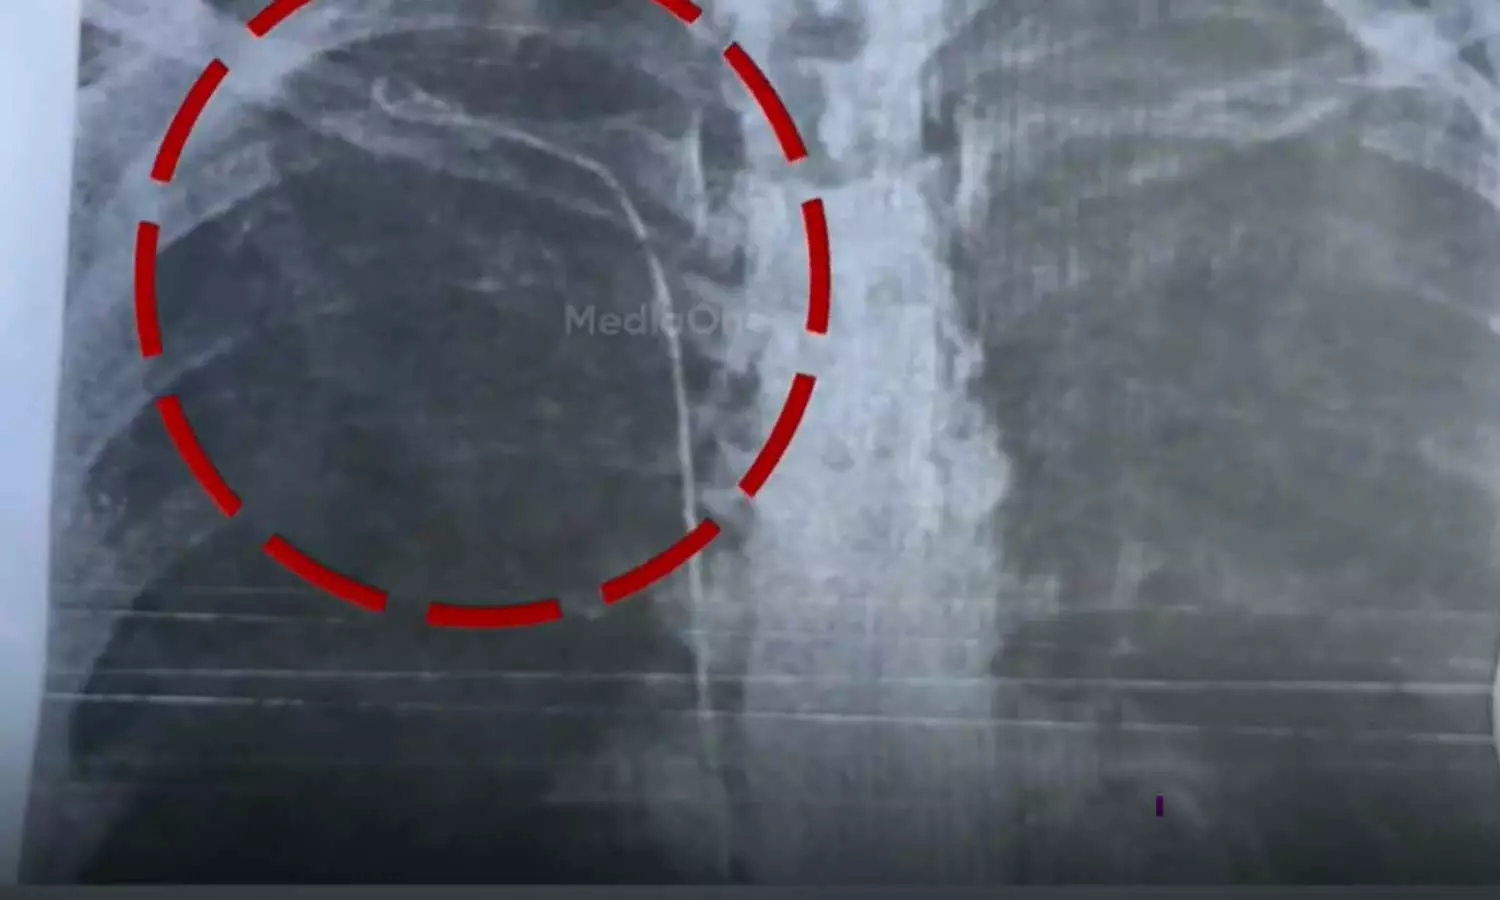

തൈറോയ്ഡ് ശസ്ത്രക്രിയക്ക് വിധേയയായ രോഗിയുടെ നെഞ്ചിലാണ് 50 സെന്റീമീറ്റര് നീളം വരുന്ന ട്യൂബ് കുടുങ്ങിയത്

തൈറോയ്ഡ് ശസ്ത്രക്രിയക്ക് വിധേയയായ രോഗിയുടെ നെഞ്ചില് 50 സെന്റീമീറ്റര് നീളം വരുന്ന ട്യൂബാണുള്ളത്. ശ്വാസംമുട്ടലിനെ തുടര്ന്ന് നടത്തിയ പരിശോധനയിലാണ് ട്യൂബ് കണ്ടെത്തിയത്. 2023 മാര്ച്ചില് കാട്ടാക്കട മലയിന്കീഴ് സ്വദേശിനി സുമയ്യക്ക് നടത്തിയ ശസ്ത്രക്രിയയിലാണ് പിഴവെന്നാണ് ആരോപണം. ബന്ധുക്കള് ഡിഎംഒയ്ക്ക് പരാതി നല്കി.

നിലവില് ഡോക്ടര് കയ്യൊഴിഞ്ഞ സ്ഥിതിയെന്ന് സുമയ്യ ആരോപിച്ചു. ട്യൂബ് നീക്കം ചെയ്യാന് കഴിയാത്ത സാഹചര്യമെന്ന് മറ്റ് ഡോക്ടര്മാര് രോഗിയുടെ ബന്ധുക്കളെ അറിയിച്ചു. നടക്കാന് ബുദ്ധിമുട്ടും ശ്വാസംമുട്ടലും ഉണ്ടാകാറുണ്ടെന്നും എന്ന് രോഗി പറയുന്നു.